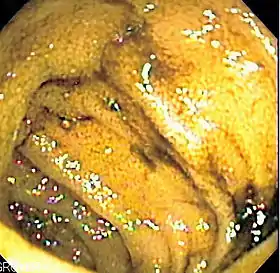

Endoscopic image of normal small bowel

Double-balloon enteroscopy, also known as push-and-pull enteroscopy, is an endoscopic technique for visualization of the small bowel. It was developed by Hironori Yamamoto in 2001.[1] It is novel in the field of diagnostic gastroenterology as it is the first endoscopic technique that allows for the entire gastrointestinal tract to be visualized in real time.[2]